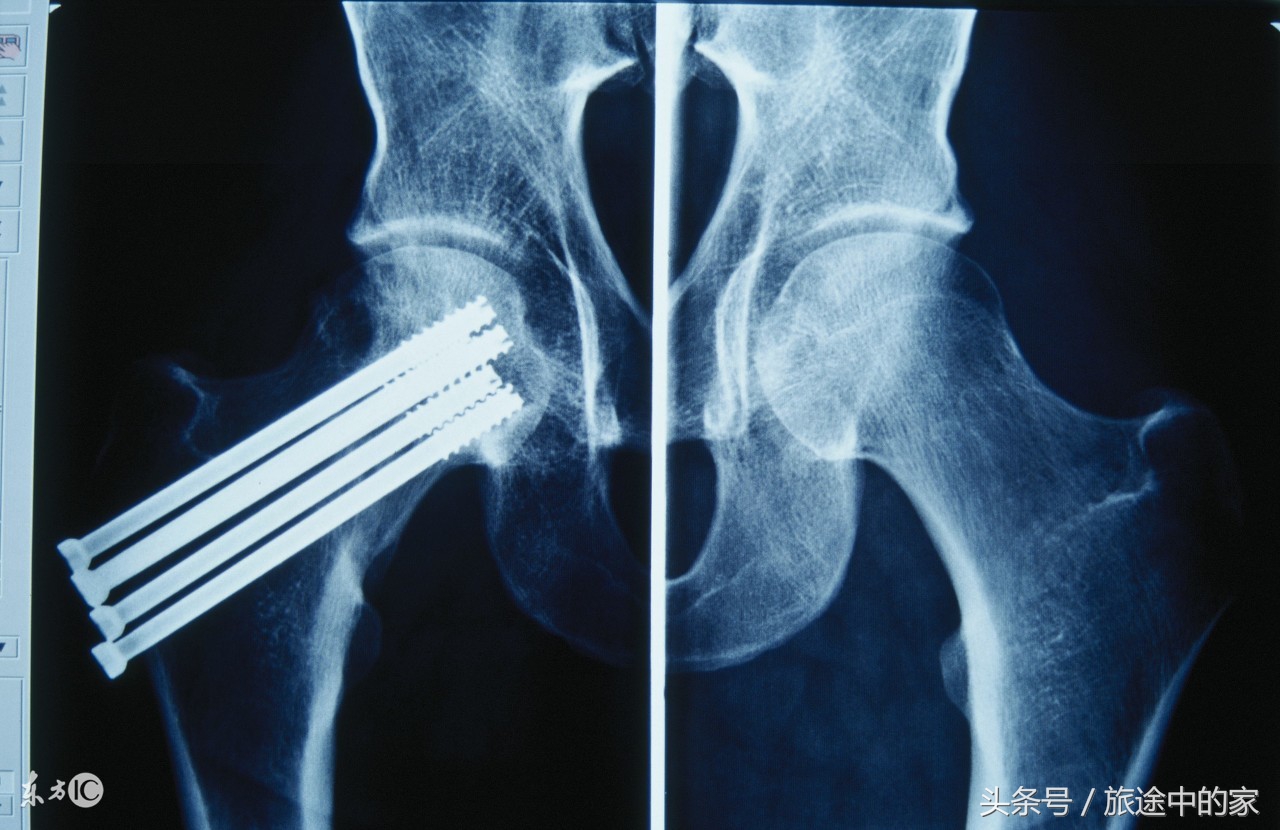

根据经验,黄东辉判断舒女士的骨折是由于骨质疏松引起的,随后的骨密度双能X线检测也证明了这一点。舒女士的骨密度T值仅为-3.0。该院开设骨质疏松门诊以来,舒女士这类病人占了相当一部分比例。

骨质疏松性骨折最常见的部位有三个:脊柱、髋部和手腕。其中,髋部骨折最危险,一年内致死率达到20%,致残率50%。